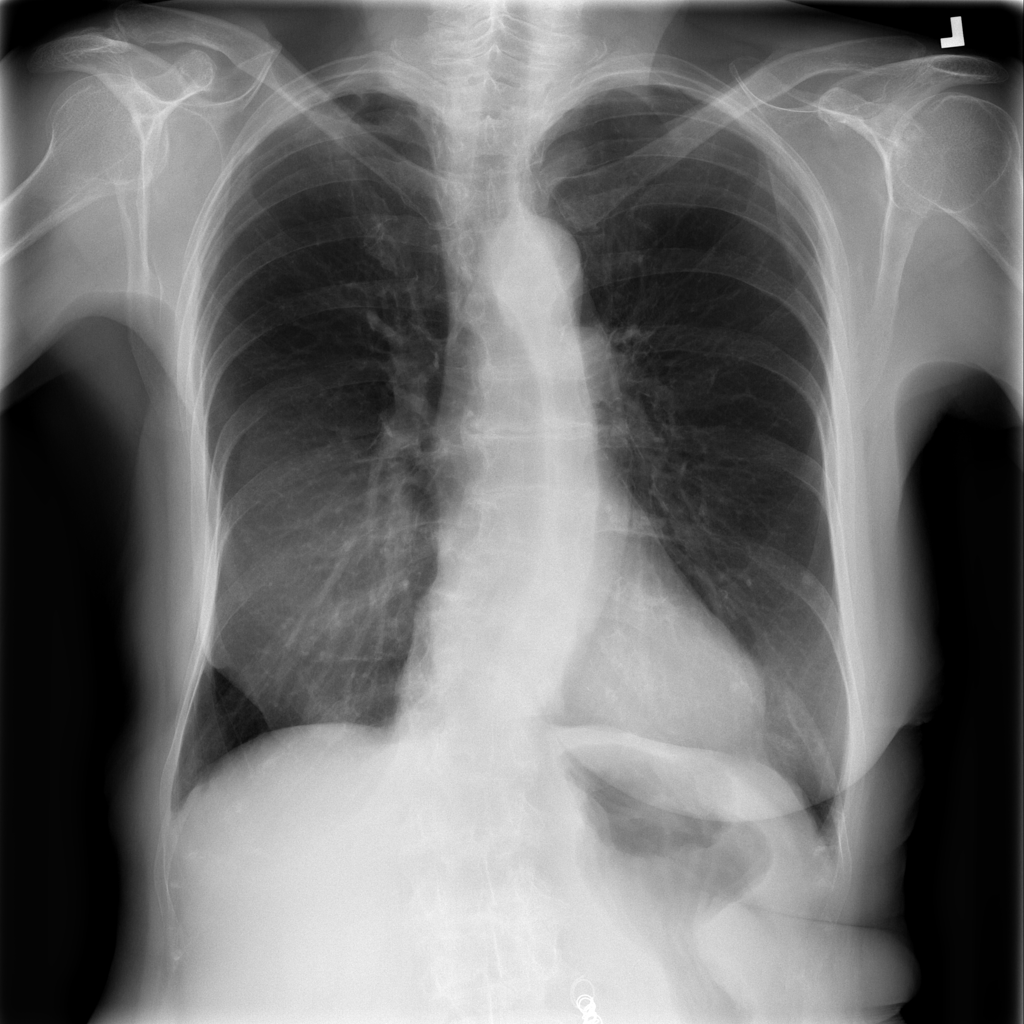

Nodule

A nodule is a small rounded opacity in the lung or chest field. It is a descriptive imaging finding that can be benign or more concerning depending on size, appearance, and context.

Showing up to 90 reference images for Nodule.

PAT-250B · IMG-000Nodule

PAT-250B · IMG-000

PA